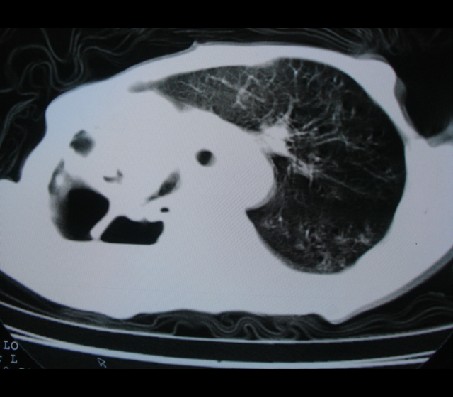

标题: CT17018:肺脓肿?左侧胸腔积液?请会诊! [打印本页]

标题: CT17018:肺脓肿?左侧胸腔积液?请会诊!

男性,65岁,有肺结核病史。

我个人意见:右侧考虑肺部感染,肺脓肿可能,胸穿穿出了脓性液体。

1)两肺继发性肺结核,右肺多发空洞形成并感染,伴左肺支气管播散。2)右侧胸膜增厚、粘连。3)纵隔疝(左→右)。

1)两肺继发性肺结核伴右肺毁损,右肺多发空洞及肺大泡形成并感染,伴左肺支气管播散。右侧液气胸.2)右侧胸膜增厚、粘连。3)纵隔疝(左→右)。